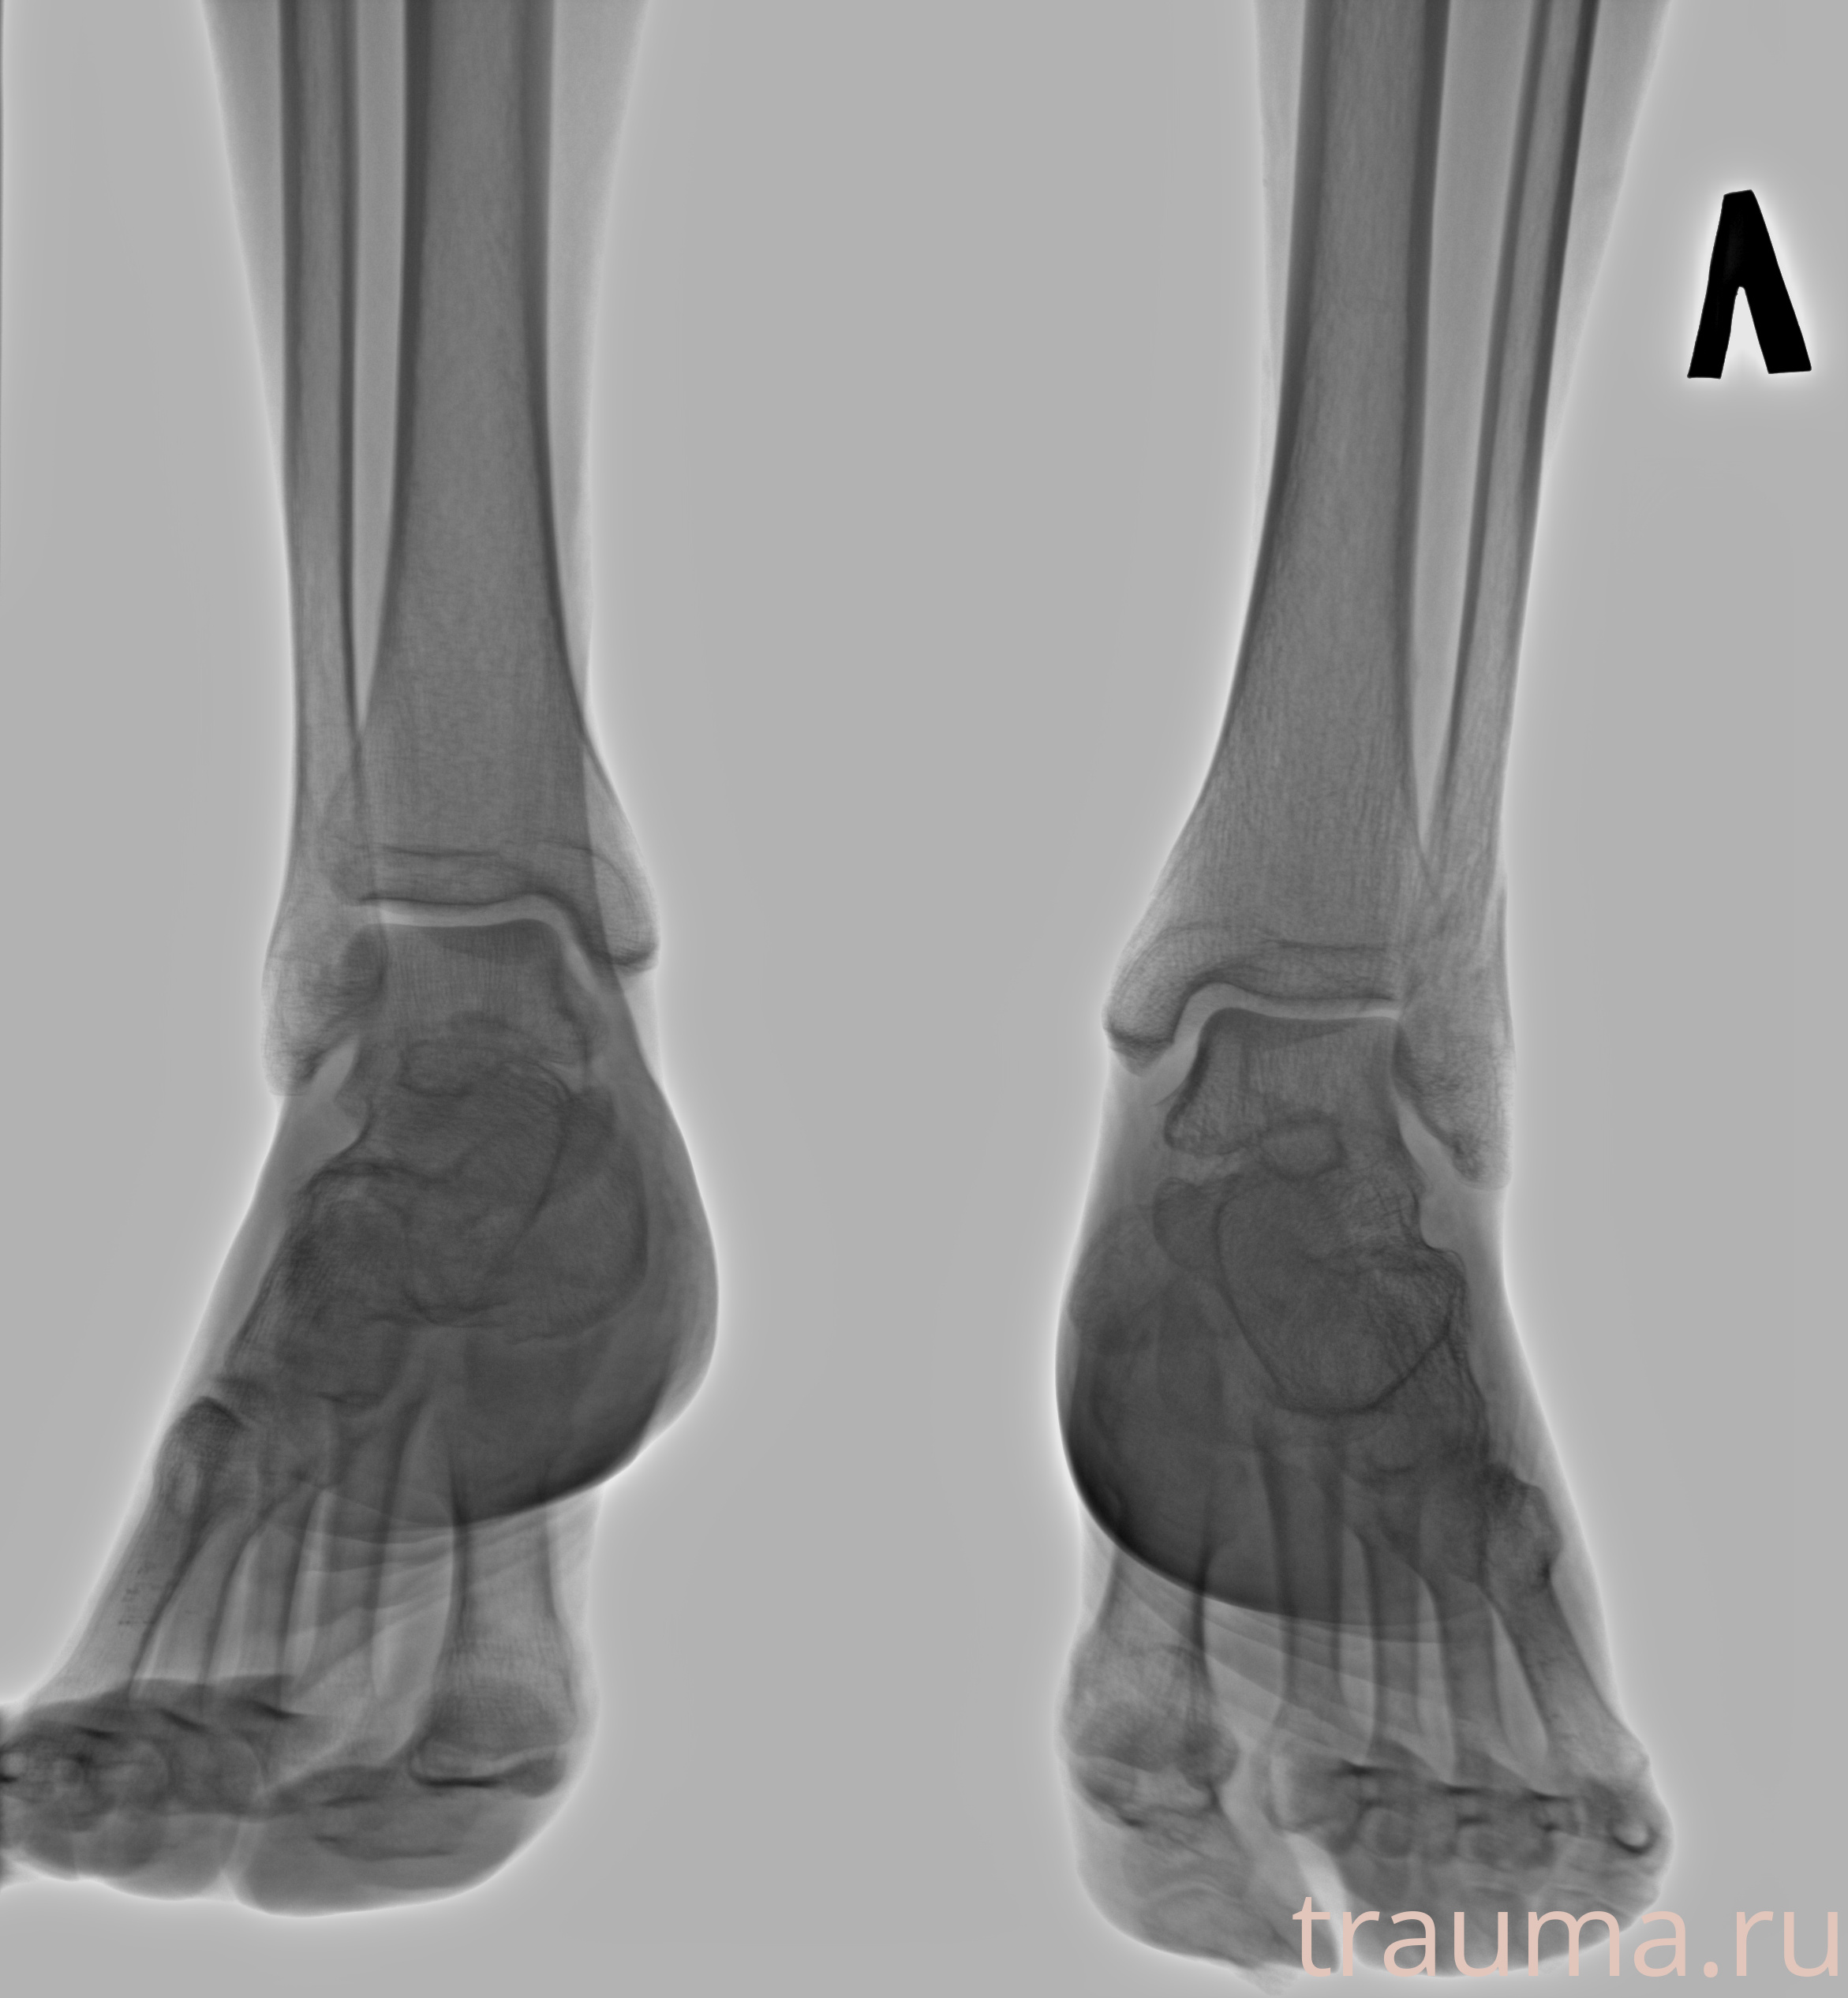

Рентгенограммы

Рентген на дому: по вашему адресу приезжает врач-рентгенолог, травматолог-ортопед с мобильным рентгеновским аппаратом, проводит диагностику травмы или заболевания, делает необходимые рентгенограммы, дает рекомендации по дальнейшему лечению. Получить качественные снимки в домашних условиях возможно благодаря уникальной методике, разработанной МосРентген Центром для института  Склифосовского

Яркость: 1   Контраст: 1   Инвертировать: 0 Увеличение: 1

Перетаскивайте мышь вверх/вниз для контраста, влево/право для яркости. Прокрутка колесом изменяет масштаб. Нажмите Сбросить для возврата к исходному изображению. При увеличении держите мышь в той области, которую хотите рассмотреть.